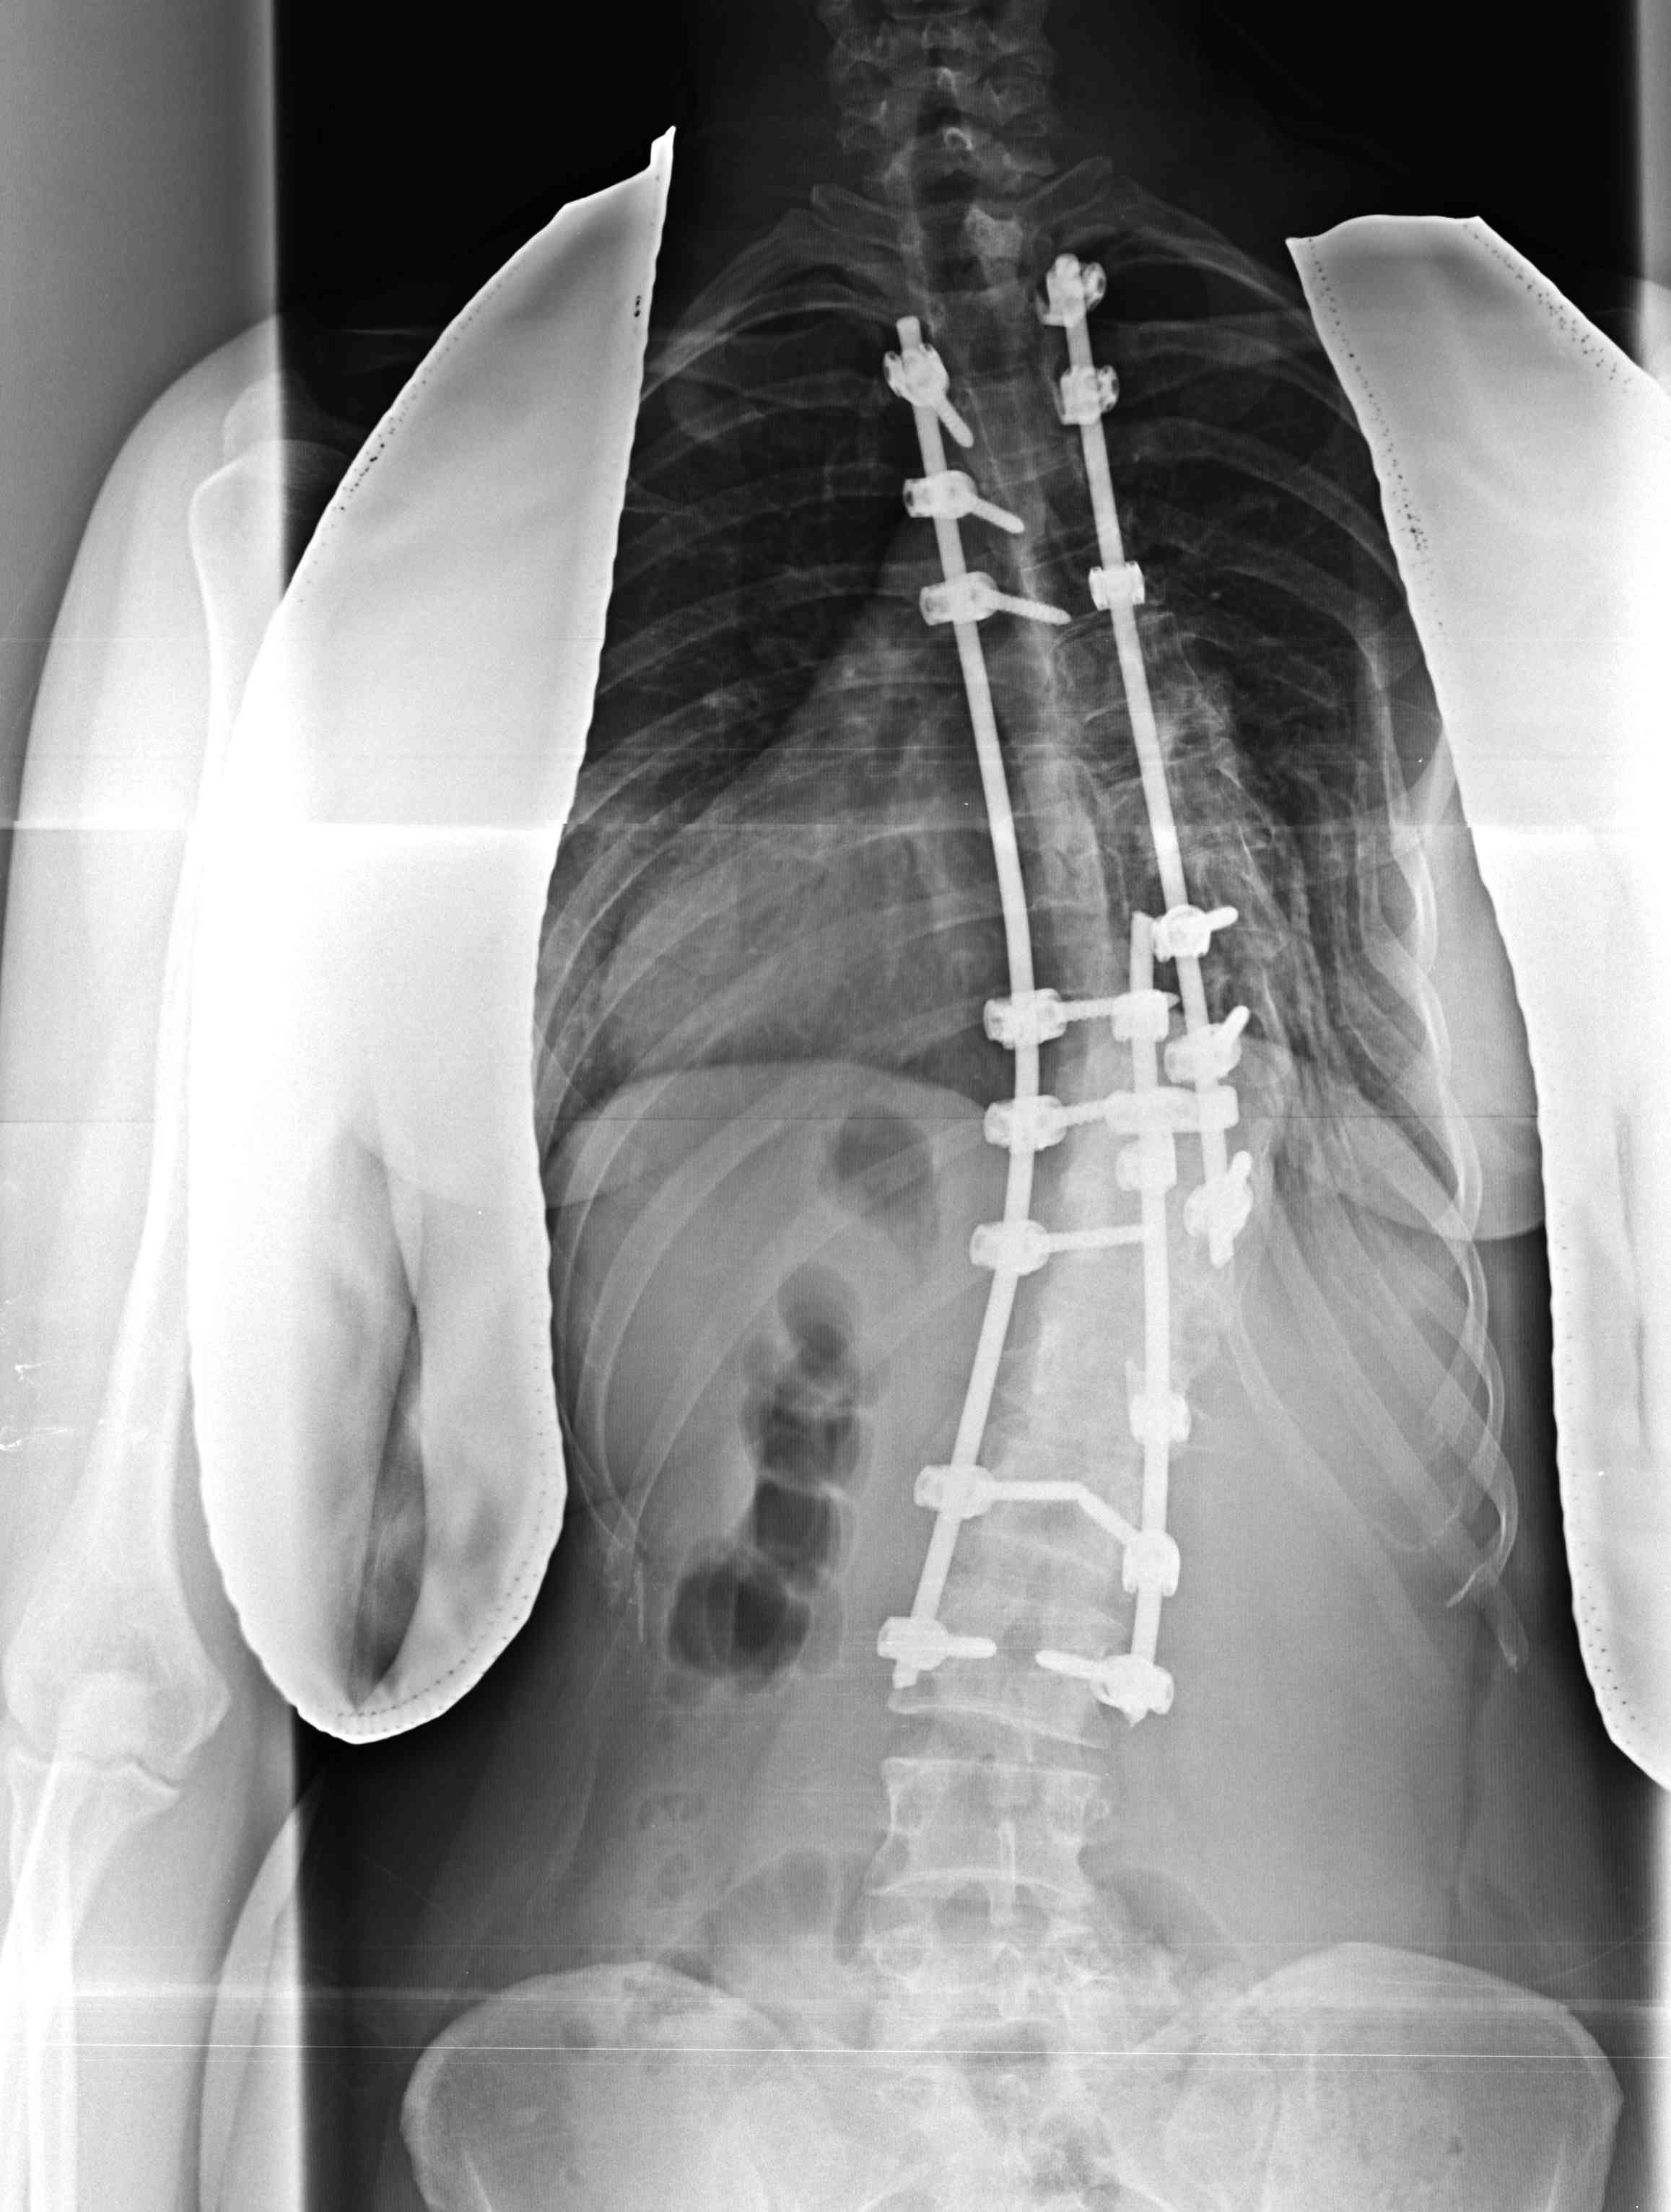

Posterior Instrumented fusion

Multisegmental Hook and Pedicle screw systems

- allows for correction via Compression / Rotation / Distraction

2 x rods prebent in sagittal plane

- correct coronal malignement and rotation as able

- may use sublaminar wires if large long curve

- midsection of curve in concavity

- tie over rod and tighten to correct

Decorticate lamina, add bone graft along each side